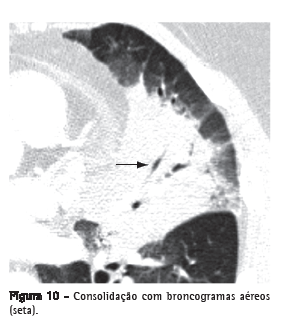

Broncograma aéreo

Tradução radiológica da identificação de brônquio(s) contendo ar, circundado(s) por parênquima pulmonar doente, onde o ar dos espaços aéreos foi substituído por um produto patológico qualquer, radiologicamente mais denso que o ar (por ex.: transudato, exsudato, sangue, produto de acúmulo ou células neoplásicas). Em geral, é a expressão utilizada quando se identifica uma imagem tubular gasosa (hipodensa), no interior de uma área de pulmão opacificado (Figuras 3 e 10). Essa imagem tubular deve ter o tamanho e a orientação usual de um brônquio ou de vários brônquios, presumivelmente representando um segmento da árvore brônquica.(22,23)

Consolidação

Representa o preenchimento, com substituição do ar, dos espaços alveolares por um produto patológico qualquer, como, por exemplo, exsudato inflamatório (pneumonia), transudato (edema), sangue (hemorragia alveolar), lipoproteína (proteinose alveolar), gordura (pneumonia lipoídica), células (carcinoma bronquioloalveolar, linfoma, pneumonia em organização) ou conteúdo gástrico (pneumonia aspirativa).(32) Na TC, manifesta-se como um aumento da atenuação do parênquima pulmonar que impede a visualização dos vasos e dos contornos externos das paredes brônquicas. Broncogramas aéreos podem ser encontrados (Figuras 3 e 10). O valor de atenuação do parênquima consolidado, ao exame de TC sem contraste, raramente é útil no diagnóstico diferencial, exceto em algumas situações (por ex.: baixa atenuação na pneumonia lipoídica e alta atenuação na toxicidade por amiodarona).(33,34)

Corresponde aos espaços contidos pelas paredes alveolares, incluindo-se os sacos e ductos alveolares, e os alvéolos nas paredes dos bronquíolos respiratórios.(43) O termo pode ser utilizado em associação com consolidação, opacidade ou nódulos para caracterizar a origem dessas lesões nesta região anatômica pulmonar, através do preenchimento desses espaços por líquido ou células. O sinal do broncograma aéreo (Figuras 3 e 10) é a marca registrada do preenchimento do espaço aéreo. Ver também Broncograma aéreo.